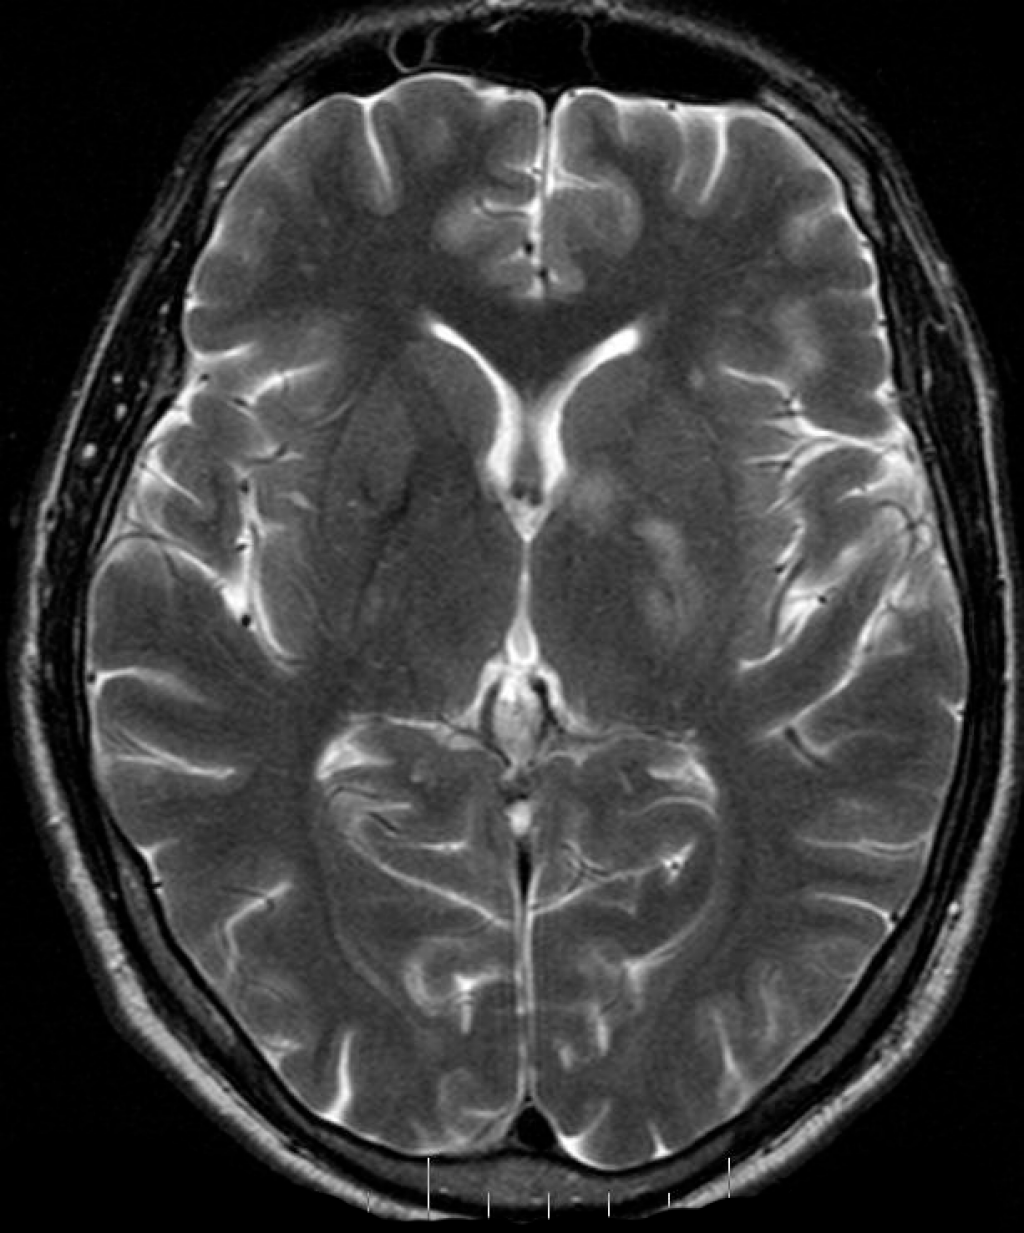

Ишемический инсульт левой стороны: симптомы и реабилитация